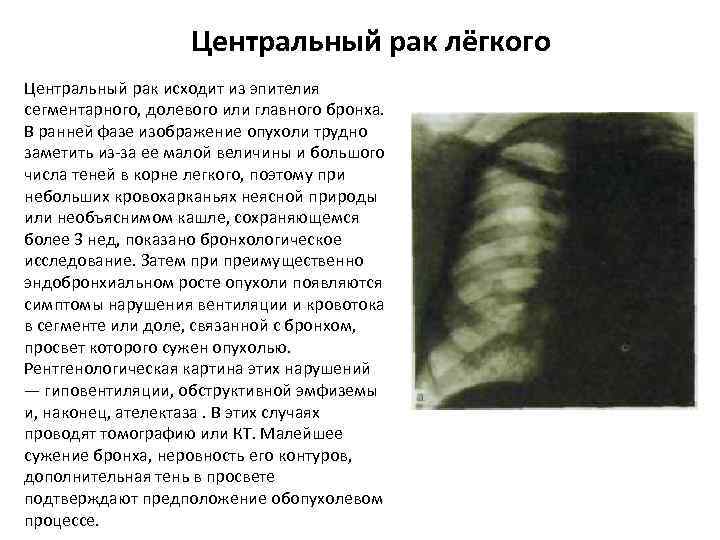

Центральный рак лёгкого Центральный рак исходит из эпителия сегментарного, долевого или главного бронха. В ранней фазе изображение опухоли трудно заметить из-за ее малой величины и большого числа теней в корне легкого, поэтому при небольших кровохарканьях неясной природы или необъяснимом кашле, сохраняющемся более 3 нед, показано бронхологическое исследование. Затем при преимущественно эндобронхиальном росте опухоли появляются симптомы нарушения вентиляции и кровотока в сегменте или доле, связанной с бронхом, просвет которого сужен опухолью. Рентгенологическая картина этих нарушений — гиповентиляции, обструктивной эмфиземы и, наконец, ателектаза. В этих случаях проводят томографию или КТ. Малейшее сужение бронха, неровность его контуров, дополнительная тень в просвете подтверждают предположение обопухолевом процессе.

Центральный рак лёгкого Центральный рак исходит из эпителия сегментарного, долевого или главного бронха. В ранней фазе изображение опухоли трудно заметить из-за ее малой величины и большого числа теней в корне легкого, поэтому при небольших кровохарканьях неясной природы или необъяснимом кашле, сохраняющемся более 3 нед, показано бронхологическое исследование. Затем при преимущественно эндобронхиальном росте опухоли появляются симптомы нарушения вентиляции и кровотока в сегменте или доле, связанной с бронхом, просвет которого сужен опухолью. Рентгенологическая картина этих нарушений — гиповентиляции, обструктивной эмфиземы и, наконец, ателектаза. В этих случаях проводят томографию или КТ. Малейшее сужение бронха, неровность его контуров, дополнительная тень в просвете подтверждают предположение обопухолевом процессе.